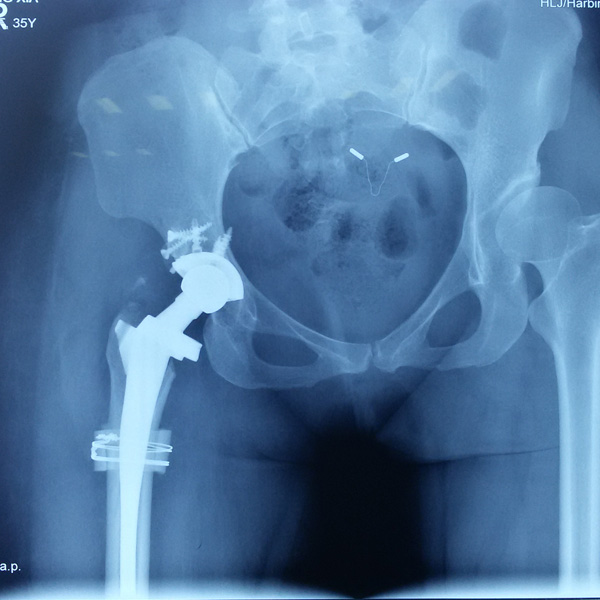

先天性髖關節(jié)脫位

患者王某某,女,41歲,從會走路以來就發(fā)現(xiàn)一條腿長,一條腿短,也就是人們俗稱的“跛子”,之前雖然兩條腿長短不一,但起碼還可以走路,維......